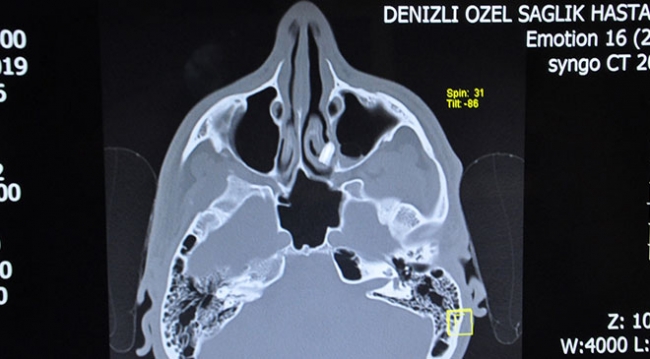

Kulak Burun Boğaz Uzmanı Dr. Ali Yüksel tarafından yapılan muayenede hastanın burnunda kemik eğriliği ve burun eti büyümesi tespit edildi, ardından çekilen yüz tomografisinde ayrıca bir cisim olduğu belirlendi.

Dr. Yüksel, hastanın tomografisinde belirlenen yabancı cismi önce kalem kapağı sandıklarını söyledi.

"Burnundaki yabancı cismi de çıkardık. Cisim, sol orta burun etine gömülmüş haldeydi. Cismi incelediğimizde diş kökü olduğu gördük. Literatüre de baktığımızda böyle vakanın çok az olduğunu gördük. Hastamızın başına bisiklet kazası sonucunda gelen bir olay. Diş, burunda 6 yıl boyunca kalmış, soluk borusuna ya da yemek borusuna kaçmayıp, enfeksiyon bile ortaya çıkarmaması bir şans."